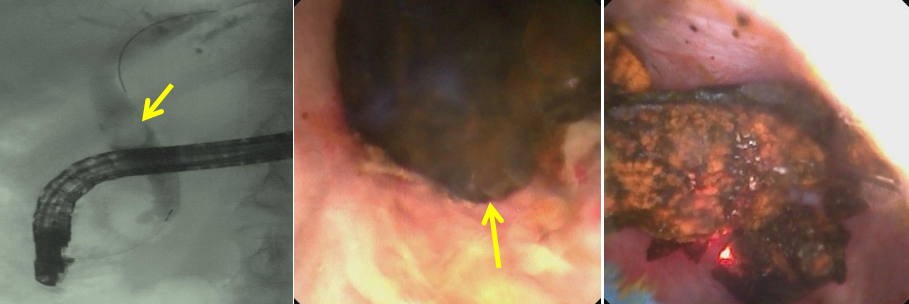

手术当天,尽管患者脆弱的心功能给麻醉带来极大的挑战,但经验丰富的麻醉科副主任王俊教授带领王爽医生迎难而上,有条不紊为患者实施麻醉诱导、插管全身麻醉,术中通过动脉穿刺实时精确监测血压,确保患者生命体征平稳。在麻醉科的有力保障下,ERCP手术团队通过激光碎石结合机械碎石的方式进行处理。但意外发现,部分碎石嵌顿于左肝内胆管起始部,常规DSA下导丝反复尝试均无法进入左肝内胆管取石。关键时刻,团队启动术前制定的应急预案,采用胆道子镜直视下超选左肝内胆管,成功后沿导丝置入取石网篮及取石球囊,逐步将碎石取出。经过2个多小时的艰苦奋战,嵌顿的胆管结石被彻底清除。

左图箭头所指为嵌顿胆管结石,中图箭头所指为子镜下嵌顿胆管结石,右图为子镜下激光碎石